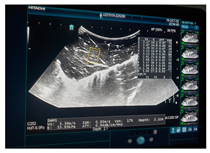

| Ultrasound | ![]() | ![]() | ![]() |